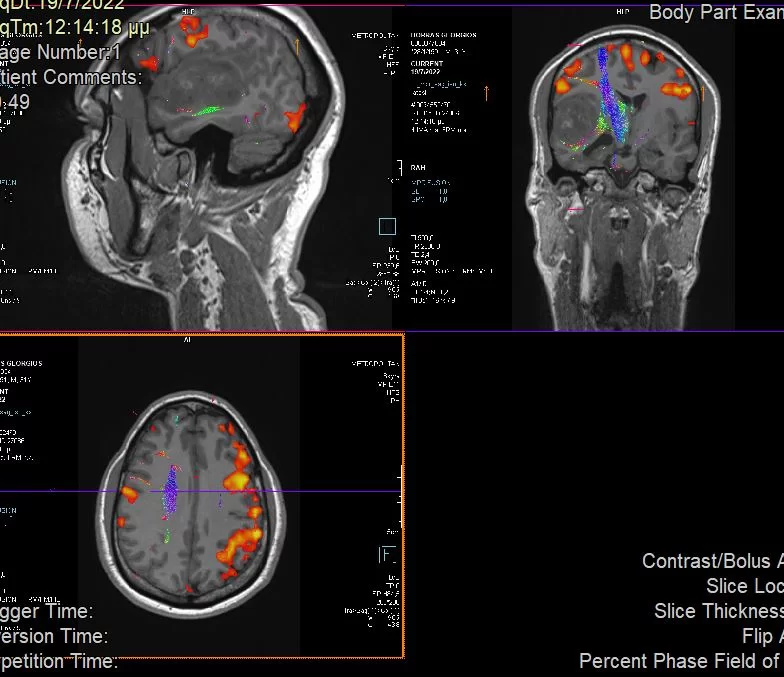

Αρχικά διενεργήθηκε ενδελεχής έλεγχος στα πλαίσια προετοιμασίας της χειρουργικής επέμβασης (οπτικά πεδία: φυσιολογικά), λειτουργική μαγνητική τομογραφία (fMRI) και δεσμιδογραφία).

Προεγχειρητικά ο όγκος και η σχέση του με τις σημαντικές ανατομικές δομές και λειτουργίες μελετήθηκε με τη βοήθεια της λειτουργικής μαγνητικής και της μαγνητικής δεσμιδογραφίας. Με απλά λόγια, αυτές οι εξετάσεις μας έδειξαν πόσο μακριά είναι ο όγκος από όλα εκείνα τα στοιχεία που θέλουμε να προφυλάξουμε.